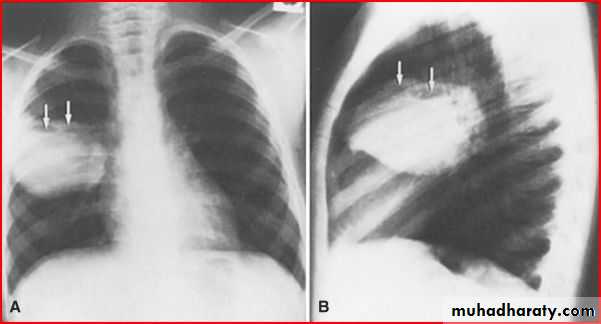

Hx of FB

A showing normal x rayB xray during expiration showing lt. lung emphysema make shifting of mediastinum